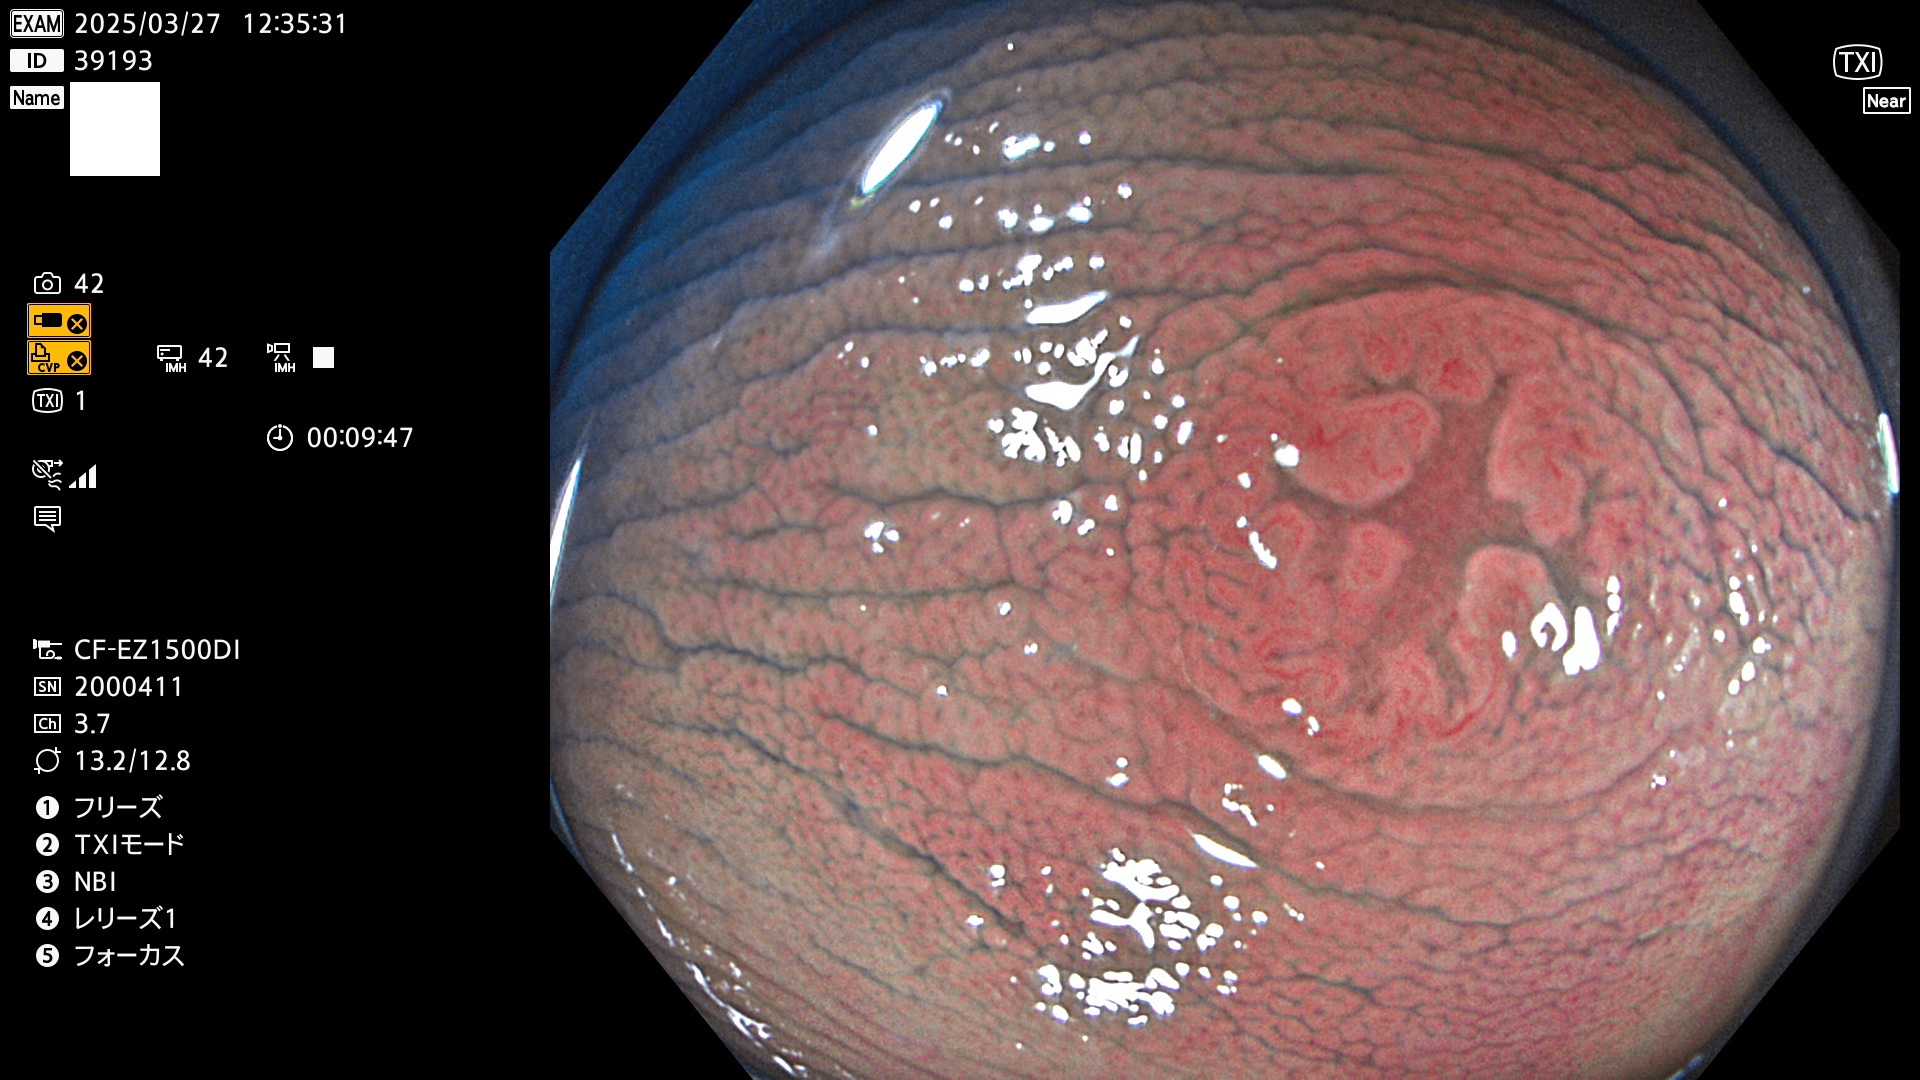

抽出の対象期間 2025年3月27日〜3月30日の4日間(48件の検査)8個 (8/48=16%)